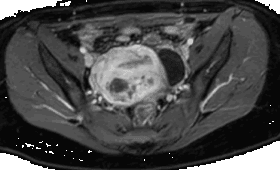

La adenomiosis es una condición benigna caracterizada por la presencia de glándulas endometriales y estroma que invaden el miometrio con presencia de hiperplasia e hipertrofia de las fibras musculares lisas. Ocurre principalmente en

mujeres entre la cuarta y quinta década de la vida, los factores de riesgo asociados son multiparidad, cirugía uterina previa y presencia de endometriosis; y al igual que este último, también es sensible a los estrógenos. MÁS